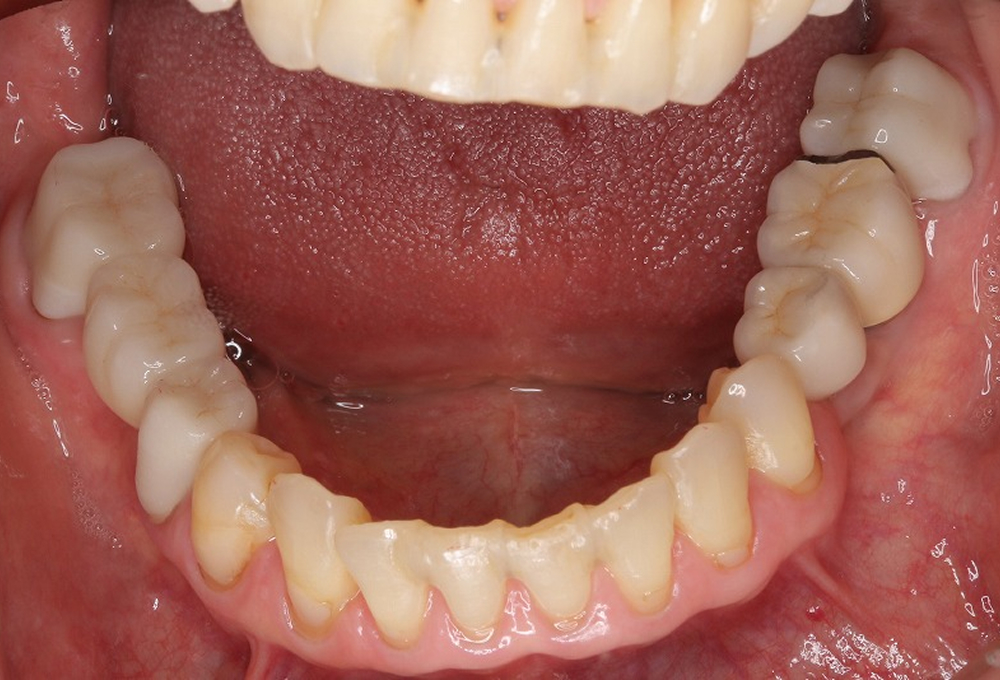

③術前下顎